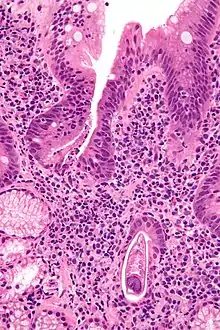

Micrograph showing strongyloidiasis; a fragment of a worm is seen in the lower right hand corner. H&E stain. | |